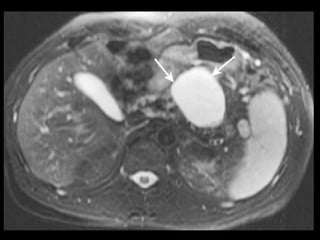

Pâncreas anular

A RM e a TCMD mostram tecido pancreático

circundando o duodeno, que conserva a densidade

e a intensidade de sinal do pâncreas normal

remanescente, tanto no exame basal como após a

administração de contraste.

Imagens T1 com supressão de gordura são úteis.

Diferenciação com neo pancreática ou duodenal.

T1: tecido pancreático ao redor da segunda porção